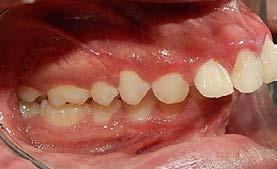

Campus Tijuana, no refiere datos patológicos ni alérgicos. Perfil facial cóncavo, sonrisa falsa (Figura 1).

Se observa dentición permanente, 28 dientes erupcionados, el canino

superior derecho y el canino superior izquierdo se encuentran en una posición ectópica, líneas medias dentales no se pueden determinar por mordida cruzada, forma de arco superior e inferior elipsoidal, clase I

molar bilateral y clase canina no se puede determinar por la posición de los mismos. Presenta crecimiento horizontal con retroinclinación de incisivos superiores (Figura 2).

A nivel radiográfico podemos observar densidad ósea uniforme, la presencia de 4 gérmenes dentarios correspondientes a los terceros molares y una relación corona-raíz 2:1. Se puede observar el patrón de crecimiento horizontal (Figura 3).